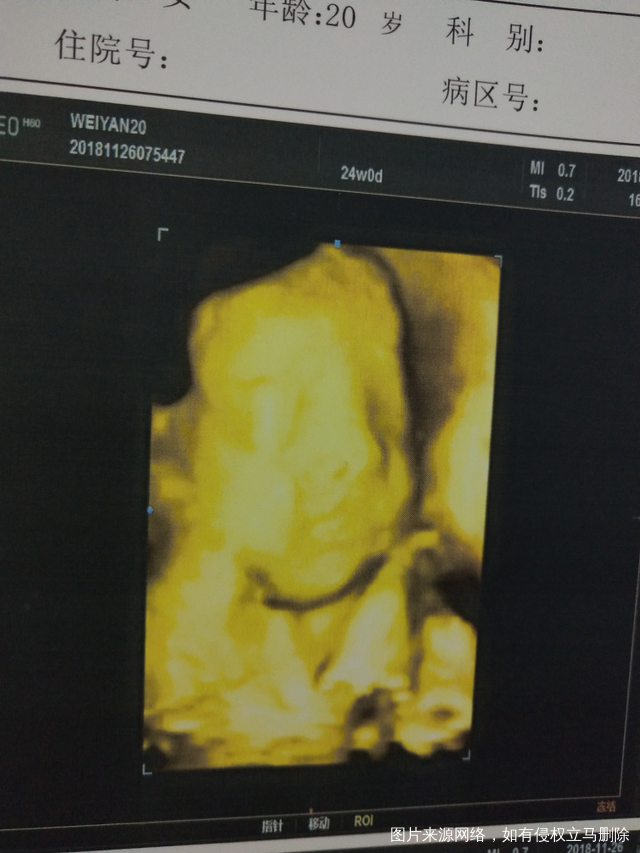

四维通过!恭喜我吧!顺便附上照片!!😃😃

5今天早上我是第一个照,起了个大早,觉也没睡好,跟你爸爸一起吃了三块钱的酱香饼,第一次有点趴着,医生一动你你就变得更趴了大概40几分钟失败了,好吧,带着你吃了根棒棒糖🍭,破例买了奶茶🍵,又吃了一碗不辣的肉丝酸辣粉🍲,爬了八层楼🏃,累得我喘大气啊!第二次还是趴着照了两分钟还是又失败了,医生叔叔又叫我去旁边的空铺侧躺🙇,大概半小时,又照依旧失败,出去有点小失望了,晒了会儿太阳☀,回来让你老爸买了巧克力🍫吃,喝了开水🍶,第三次医生又是摇又是使劲揉啊,你妈妈我的肚子都疼起来了,还是失败了,好吧,吃了个青椒土豆盖饭🍛后,又回来,继续照,医生叔叔吃了外卖继续照,结果依旧失败!你妈子我开始各种担忧啊!你老爸明天还不能陪我,有活要干了,我就在车里前排座位各种把你头头转出盆骨的方法都用尽了,之后在车里又小憩半小时午觉,结核医院跟你老爸查了痰之后又去妇幼保健院,一直我都撅着屁股,生怕你小脑袋不出盆骨,照之前又是一顿担忧☹️,进比超室最后一次,女医生阿姨告诉我你出盆骨了,能看得到,但是手挡住了脸,各种摇你,妈妈也各种说你要听话哦,乖乖的哦,给医生露个脸就带你吃好吃的,这次你学聪明了,终于露了脸!我好开心😘,两个医生都笑你了😁!嗯!最后顺顺利利的,照得算好的!很满意!去结核医院结果也都是好的,

你们说,这娃娃像男孩👦还是女孩👧呢!?😋😋😋